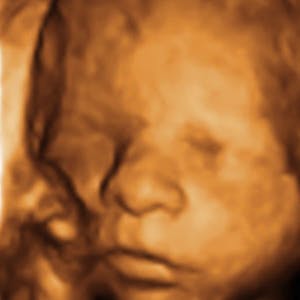

Gravid

Vi gør en dyd ud af at klæde dig godt på både før, under og efter din graviditet. Vi ved, at der kan komme mange spørgsmål til din graviditet, fødsel, amning, din babys udvikling og mange flere emner, derfor har vi samlet guides, tips & tricks samt læsernes egne fortællinger i dette gravid univers.